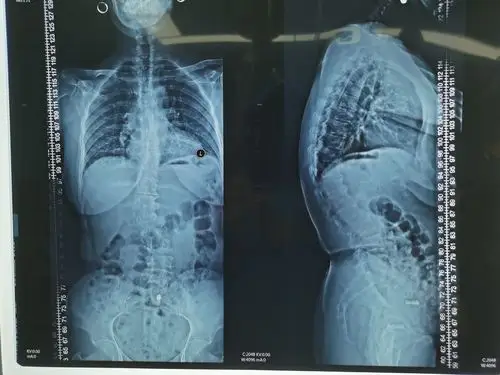

x线,ct,mri等,来观察患者的脊柱结构和功能,测量胸椎后凸的角度和范围

黎燕清,女,56岁,胸椎后凸畸形,t8,9椎体骨折,as并al,op,清远职工医保

胸腰段后凸cobb角42度,侧凸约20度.